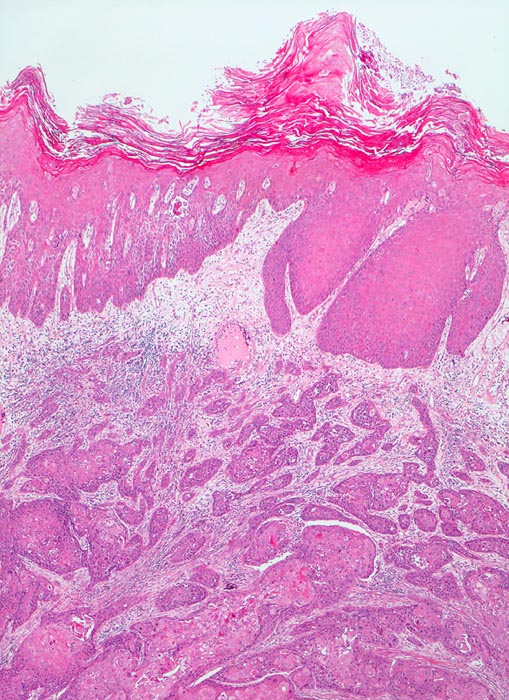

Plattenepithelkarzinom der Harnblase

Der zytologische Befund entspricht dem der Plattenepithelkarzinome an anderen Orten. Allerdings finden sich oft auffallend wenig Tumorzellen, die überdies oft nur geringe Atypien aufweisen.